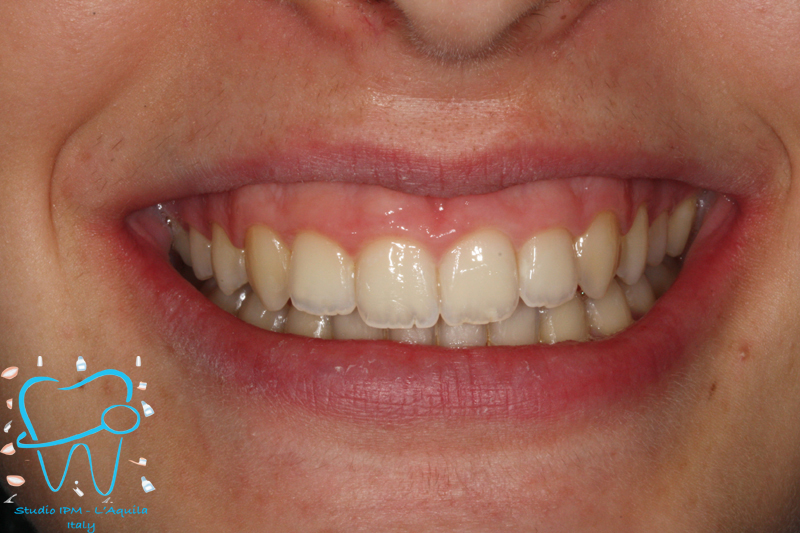

1982 visualizzazioni Una paziente di 12 anni si presenta alla nostra osservazione con una malocclusione in arcata superiore ed inferiore. La situazione appare complicata, oltre che da un affollamento notevole in arcata superiore, dalla agenesia dell'elemento 4.5 e con il 3.6 molto distrutto e difficilmente recuperabile per il futuro in maniera pervedibile. Si decide a questo punto per un trattamento ortodontico fisso con il movimento mesiale degli elementi posteriori e la chiusura degli spazi solo con denti sani e pienamente funzionanti ed evitare successivamente costosi procedimenti protesici.